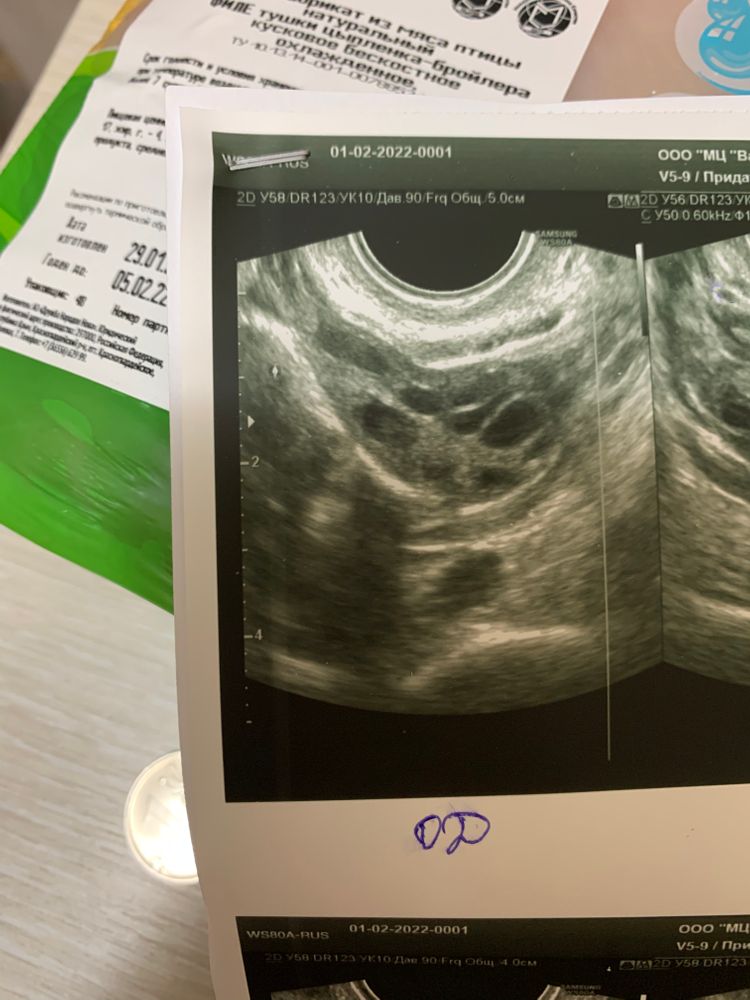

Фолликулометрия

На 9 день цикла , доминантный фолликул 8 мм.

Цикл у меня 29-30 дней.

Обычно в это время фолликул был примерно 10 уже.

Я вижу два ДФ) Дорастут, куда денутся)